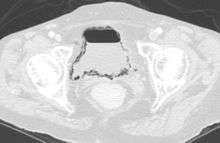

Emphysematous cystitis in computertomography

Diagnosis is made by patient history of passing air or a sputtering urine stream. CT scans may show air in the urinary bladder or bladder walls.